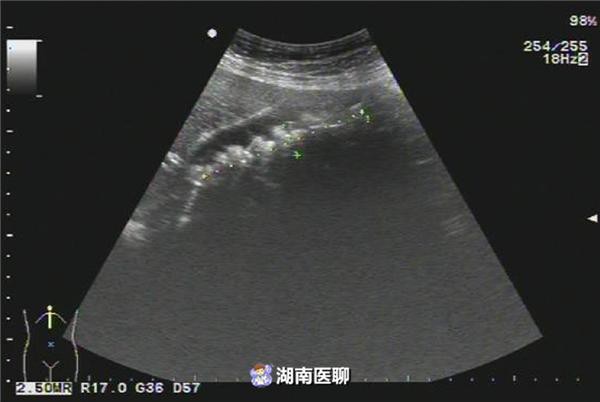

Ngày 16/8, cô Lý tiến hành phẫu thuật cắt túi mật nội soi tại bệnh viện Nhân Dân. Trải qua 1 tiếng đồng hồ, các bác sĩ đã thành công cắt bỏ túi mật, và kinh ngạc phát hiện có 258 viên sỏi túi mật hình vuông, có màu xanh nhạt.

Bác sĩ Liêu Xuân Hồng, cho biết: "Cô Lý đã từng trải qua phẫu thuật cắt bỏ ung thư dạ dày, cho nên sức chứa của khoang bụng nhỏ lại, sau khi thức ăn đi vào, khoang bụng sẽ dãn nở, kích thích túi mật co lại, bài tiết dịch mật, khiến cơ chế của túi mật suy yếu".

Điều này khiến túi mật của cô Lý duy trì tình trạng không bình thường suốt 20 năm qua, tạo nên sỏi cholesterol, hơn nữa túi mật nhiều lần bị viêm, dần hình thành sỏi cholesterol có hình dạng lớn.